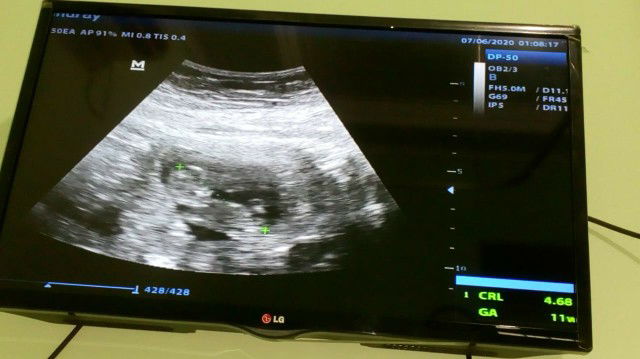

USG

USG pertama uk 11w3d adek bayi udah keliatan, seneng banget ayahnya pas pertama kali lihat adek bayi dalam perut gerak-gerak?gak berhenti ayahnya ngelusin perut Mulu?☺️sehat-sehat nak?kesayangannya ayahBunda